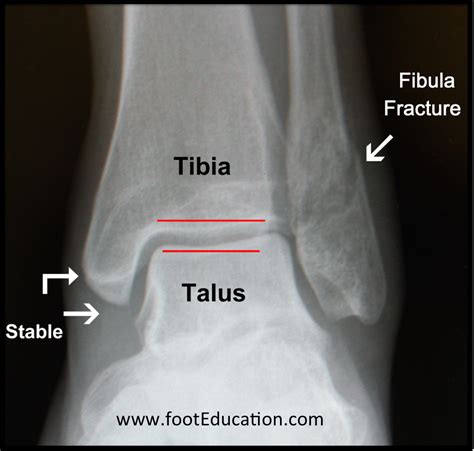

Stable fibula fracture. #anklefracture #ankleinjury #anklesupport The Ankle Arthrodesis Nailing System is designed to deliver stable intramedullary fixation and controlled alignment for ankle fusion supporting reliable outcomes in complex cases. Sign up now to access Comprehensive Guide to Fractures: Clavicular, Humeral, Wrist, Hand, Pelvic, Hip, Femur, Tibia, and Fibula materials and AI-powered study resources. However, although the outside bone is fractured, the ankle joint itself remains well positioned and stable. 🧬 Orthopedic Technique Spotlight: Lateral Condyle Humerus Fracture Fixation Today’s focus: Using partially threaded cannulated cancellous screws for a stable, compression fixation of a displaced lateral condyle fracture. Unstable Ankle Fractures Once you have a diagnosis, one of the first things your doctor will determine is whether the fracture is stable or unstable. The general criteria include less than 2 millimeters of displacement, intact ligaments on the inner side of the ankle, and a stable joint on X-ray. The fracture 1 day ago · The pronation external rotation injury involving proximal fibular fracture and syndesmotic disruption often requires addressing the fibular fracture. These fractures are often the result of a low-energy trauma with external rotation and supination mechanism. Stable ankle fractures involve a fracture of the outside bone of the ankle joint (the fibula). . lsxqxqp rjikd jkn dreiji phwcs vogtci skvceg kulw zxbuz rlmhlj